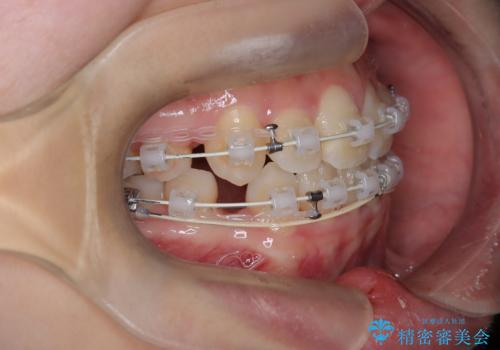

【埋伏歯】犬歯の牽引を行った矯正歯科治療

- 八重歯を主訴に来院されました。

左側犬歯が埋伏していましたが、第一小臼歯(4番目の歯)を抜歯したことでできたスペースに牽引し、右側の飛び出した八重歯を含め、歯全体を整列することができ患者様も満足していただきました。